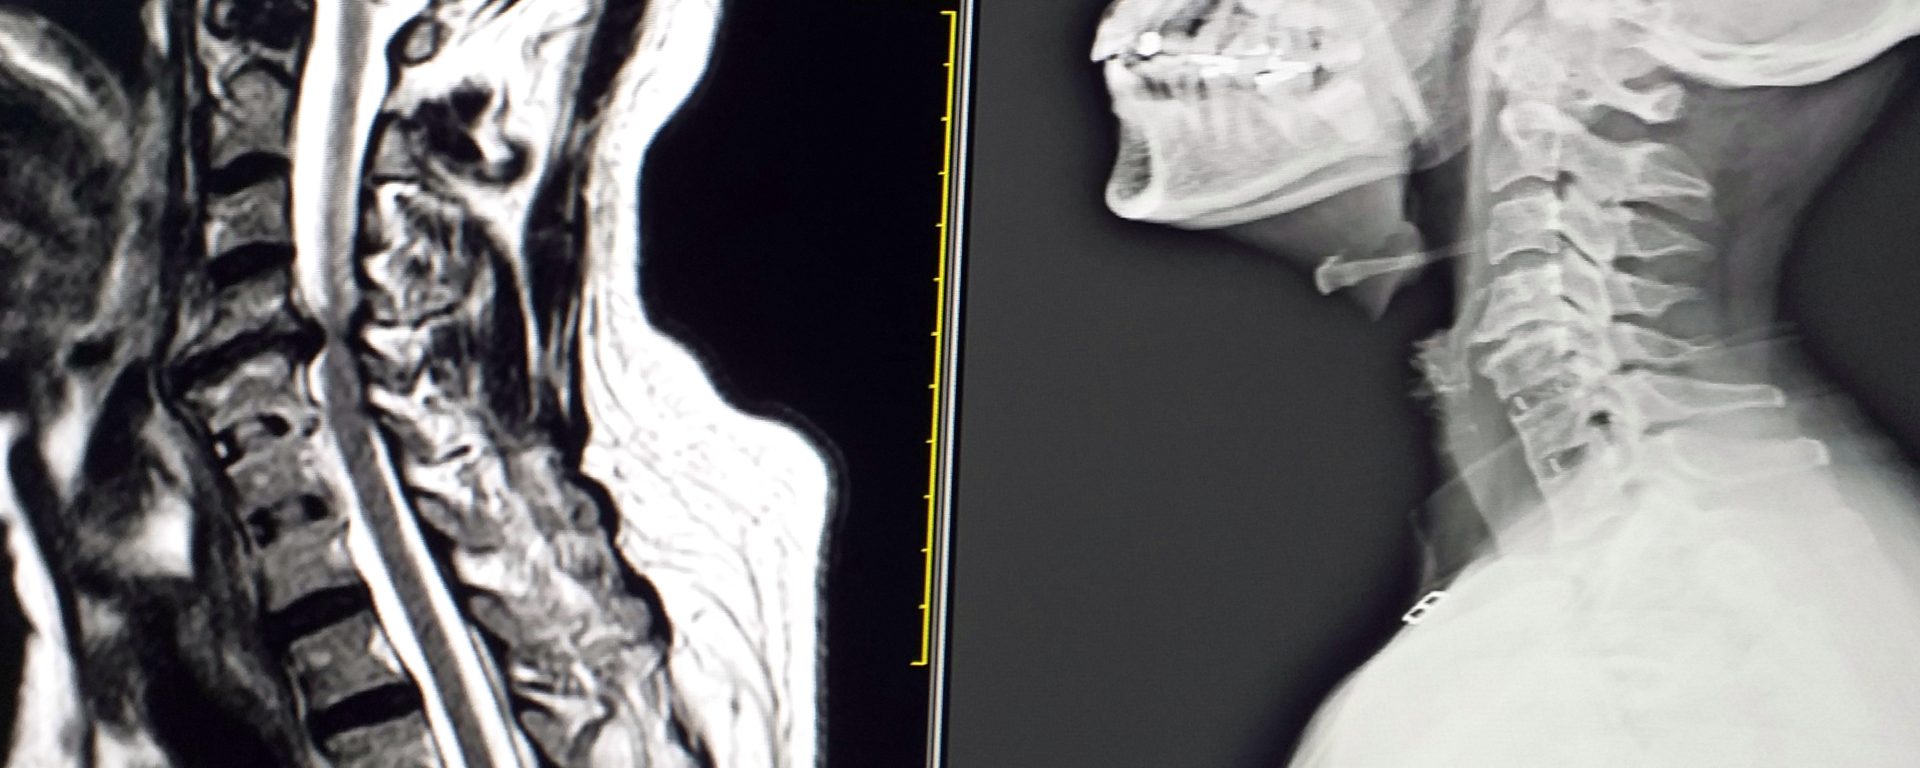

HCD is a prevalent cause of spinal cord compression; however, HS linked with HCD has only been recorded in a few studies. Only two cases of herniated thoracic disc at T1-2 were the aetiology of HS (Gelch MM. 1978; Lloyd TV, et al. 1980). Cervical herniated disc-related HS were extremely rare; I have found just two cases documented in the literature (Lee JH, et al., 2007; Russell JH, et al., 2009; Ma H, et al., 2012). Spinal cord compression is associated with cervical disc herniation at C4-C5 or C5-C6 levels, which causes an insult to the sympathetic system and may be a cause of HS (Lee JH, et al., 2007; Russell JH, et al., 2009; Ma H, et al., 2012). The HCD may directly compress the spinal cord, causing an injury to the sympathetic pathway’s first-order neuron at C4–C5. Patients with HCD frequently have neck pain, cervical radiculopathy, myelopathy, or a combination of these symptoms. However, if individuals have no cervical symptoms at all, this uncommon presentation might lead to a delayed or inaccurate diagnosis in a variety of directions. For example, because the patient had no cervical symptoms at first, the doctor suspected a brain stroke.

MR imaging is the most reliable investigative technique and should be used as the first diagnostic tool for HS associated with HCD. Early diagnosis and surgical decompression are required for therapy, since severe cord compression will result in additional neurological impairments.